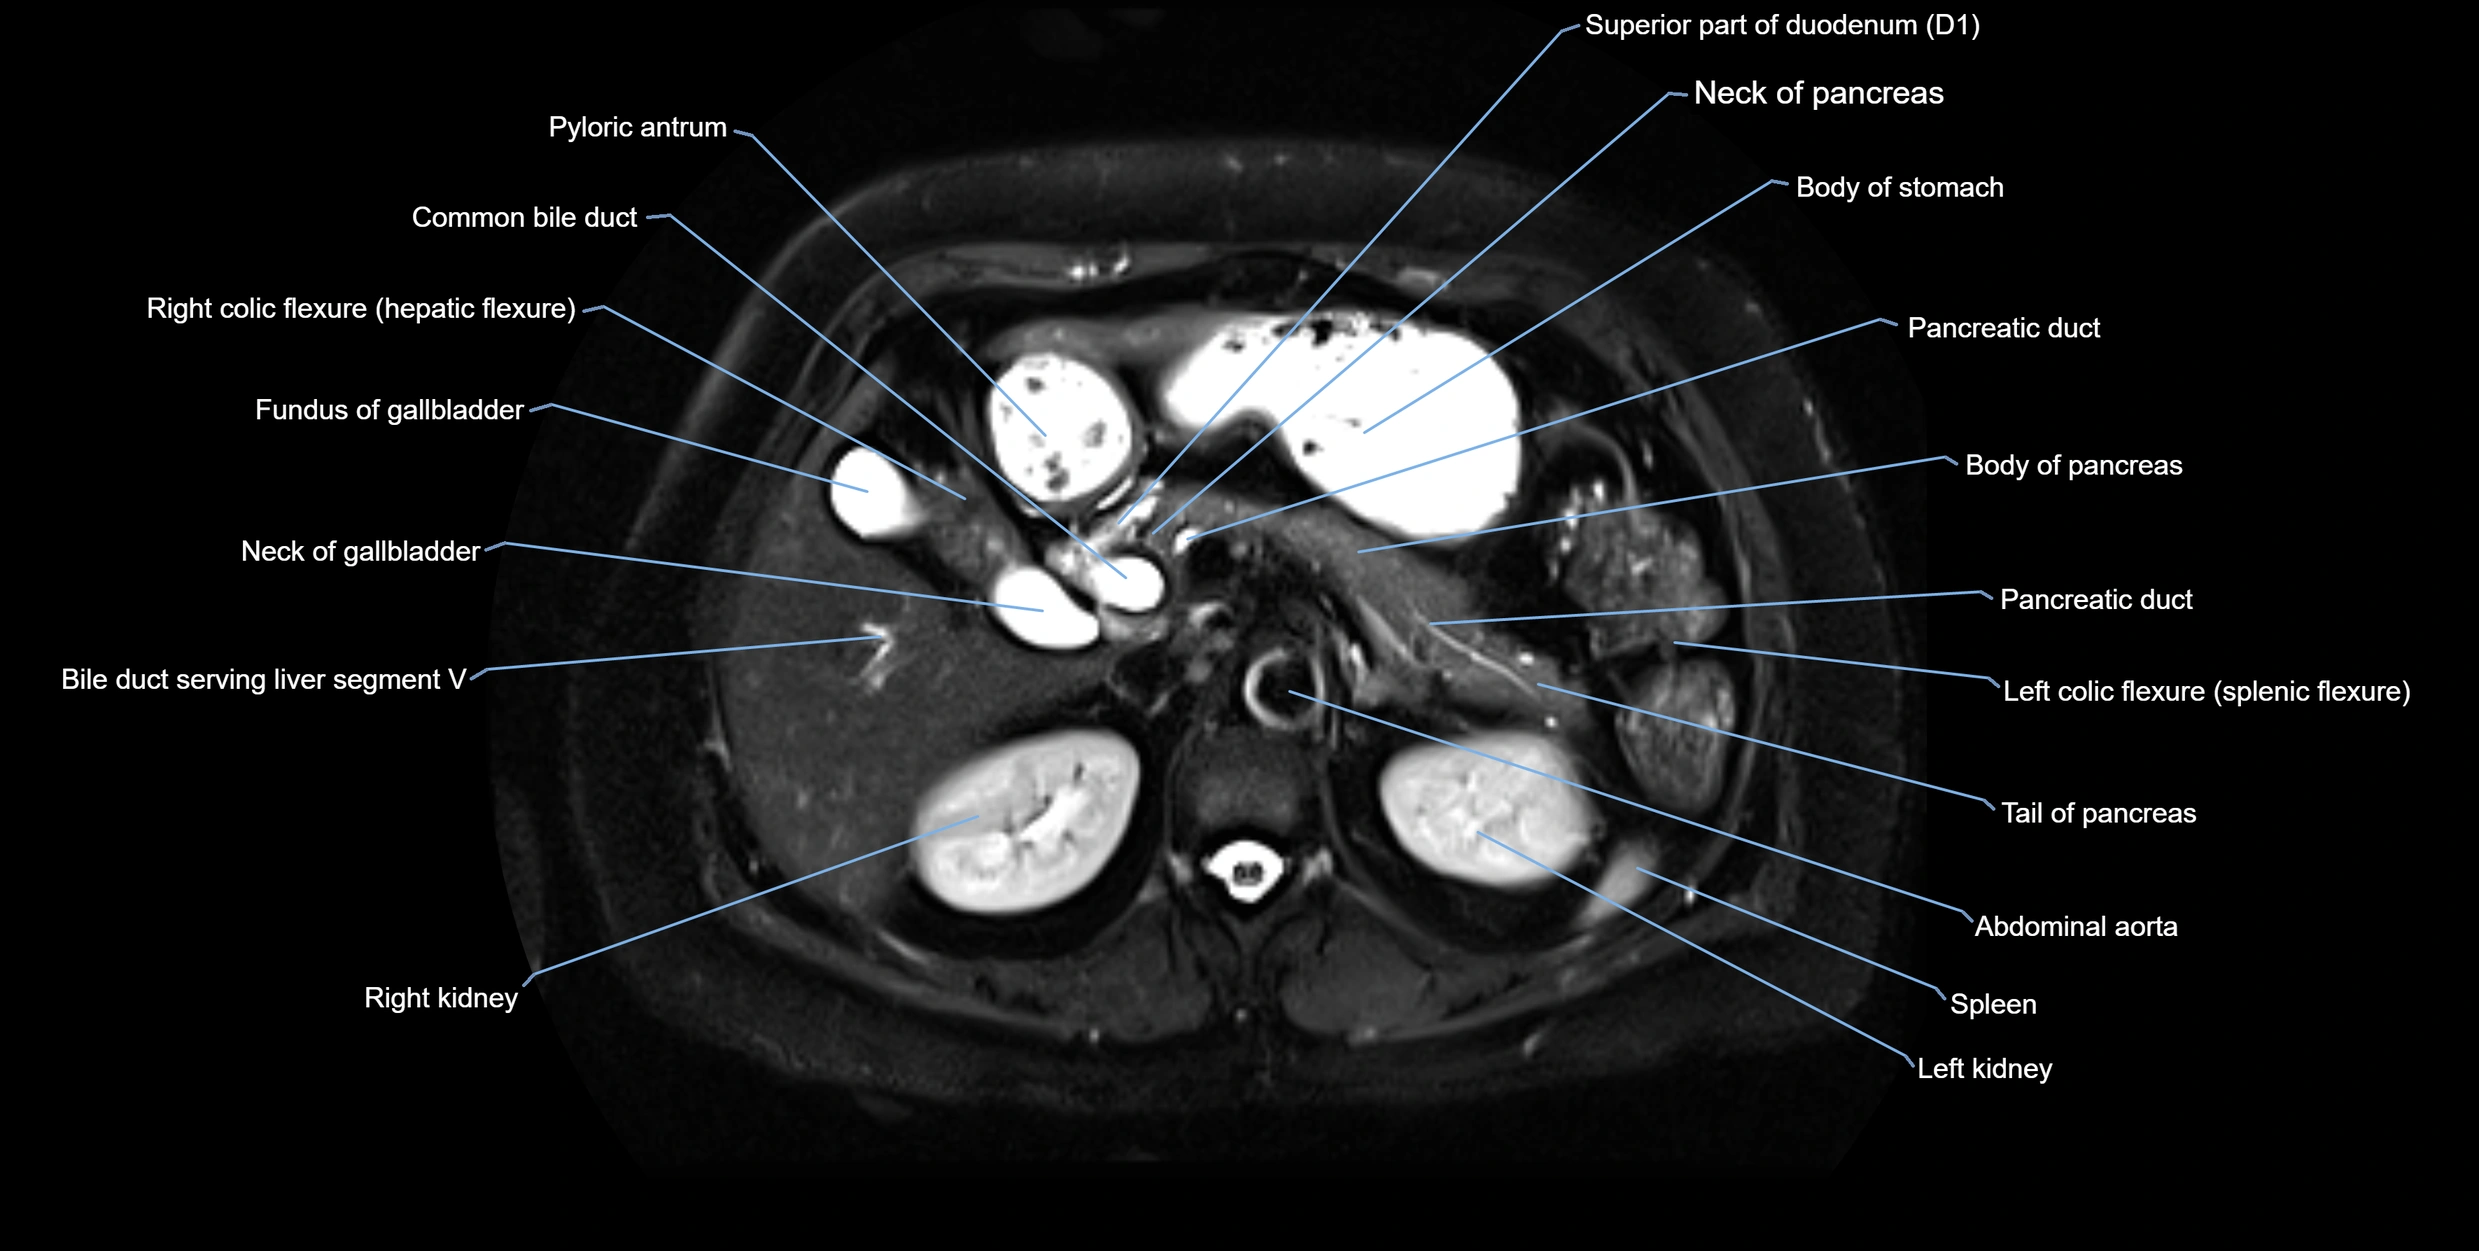

MRI image

image